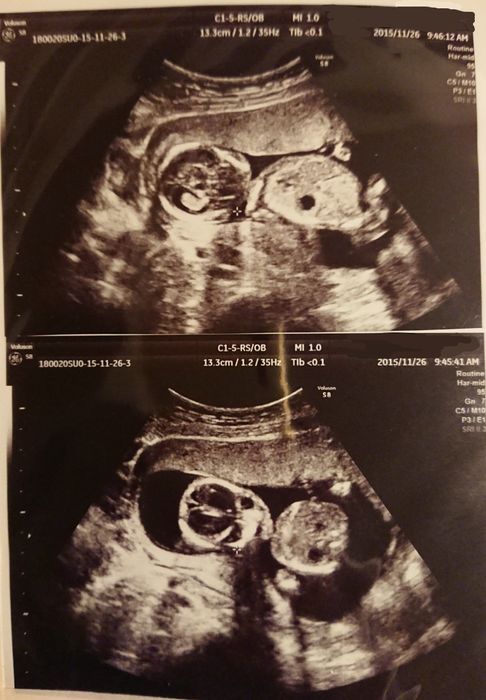

妊娠26週目 性別判明!赤ちゃんの名前が舞い降りた!

前回わからなかった性別がやっとわかりました。ドキドキして待っていると、先生が「女の子だよ! おしゃぶりの練習をしているのかな?」と。このエコー写真を見た時、突然ビビビッと感じ「メイ」と名付けようと決めました。